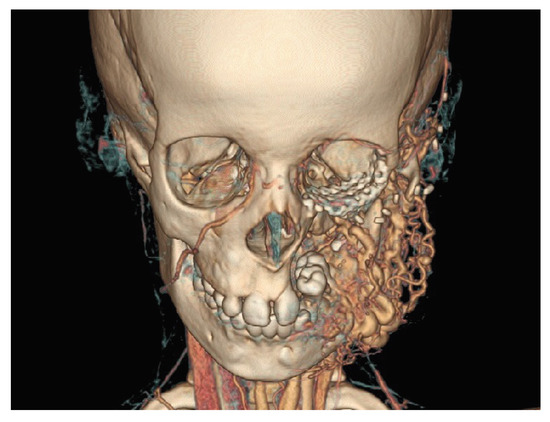

A 7-year-old girl, a case of arteriovenous malformation of left maxilla region, with a history of prior left total maxillectomy, presented with a recurrent lesion involving the ramus of the mandible. The reconstruction was first attempted with a free fibula flap, which failed, and then with an anterolateral thigh (ALT) flap which was successful. The orbital floor reconstruction was done with a titanium mesh. The computed tomographic (CT) scan at presentation showed residual arteriovenous malformation involving ramus and coronoid process of left mandible with cortical destruction (Figure 1 and Figure 2). There was no evidence of recurrence at previous operated site. A carotid angiogram showed feeders from left external carotid artery with draining veins to both internal jugular veins.

Figure 2. Three dimensional CT scan with angiogram showing the lesion involving the ramus and coronoid region of left hemi-mandible with feeders from left external carotid artery.